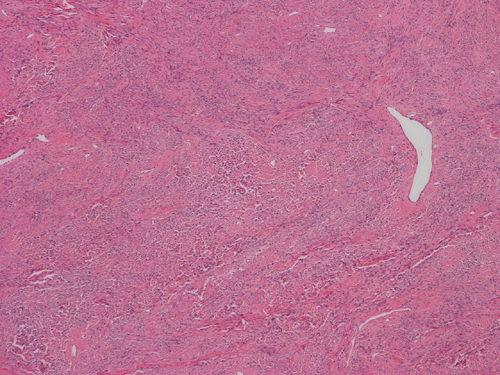

Histologically, the tumor is composed predominantly of strands of collagen fibers arranged in interlacing bundles (Panel F, G, H, I, J ). The histologic pattern is rather homogeneous among different areas and no area with particular hypocellularity or hypercellularity are found (Panel F). In between the collagen fibers are cigar shaped nuclei without high grade features (Panel J). The nuclei and the collagen fibers maintain an interesting regularly randomized relationship reminiscent of a checker board pattern (Panel I). A few small fragments of entrapped, mature bone are also found within the tumor. Mitoses and necrosis are not seen.

Immunohistochemistry demonstrated positive immunoreactivity in tumor cells for Vimentin, Bcl2 (Panel K) and CD34 (Panel L) but not CD99. The tumor cells are negative for muscle specific actin, desmin, S100, cytokeratin AE1/AE3, and epithelial membrane antigen (EMA).